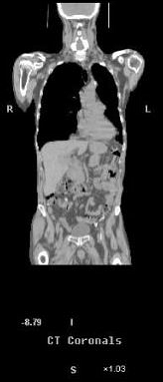

Fig. 6- Carcinom rectal - recidiva:

a) CT: formatiune presacrata de dimensiuni mari, omogena; sageata indica directia acului de biopsie, rezultatul biopsiei fiind negativ;

b) Imagine PET (18FFDG), cu fixare eterogena, demonstrand o zona tumorala activa, periferic;

c) imaginea fuzionata PET-CT demonstreaza prezenta unui inel tumoral discontinuu care inconjoara un centru necrotic; repetarea biopsiei in zona functionala a tumorii demonstreaza recidiva tumorala.